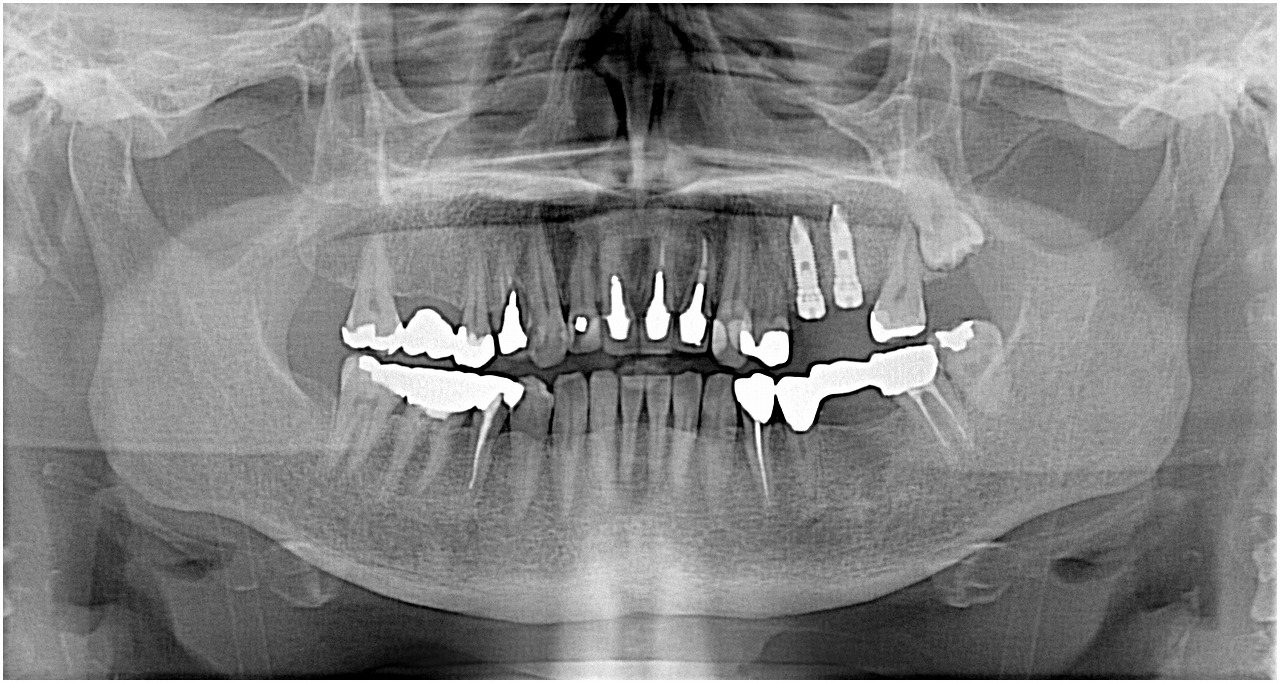

同じ方で右上の4番部が被せが脱離 パノラマでも近心部に穴が開いていました この歯も保存不能 ブリッジkさインプラントかで、、、左のインプラントが良かったのでインプラントとなりました

右上の4番部になります

術前のパノラマでもコアが近心部から出ていました